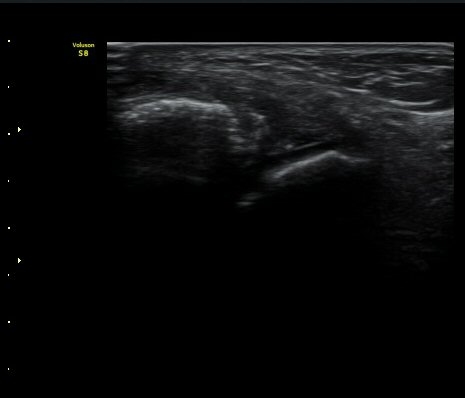

3ÁÖ ÈÄ ÃßÀû°Ë»ç»ó °üÀý³» ºÎÁ¾ÀÌ ¼Ò½ÇµÇ°í(±×¸² 4). Àü°Å°ñºñ°ñÀδëÀÇ Àú¿¡ÄÚ ºÎÁ¾ÀÌ

°¨¼ÒÇÏ°í °ß¿­°ñÀý °ñÆíÀº ºñ°ñ °¡±îÀÌ À§Ä¡Çϰí ÀÖ´Ù(±×¸² 5, 6).

±×¸²4) 3ÁÖ ÈÄ ÃßÀû°Ë»ç

±×¸²5) 3ÁÖ ÈÄ ÃßÀû°Ë»ç